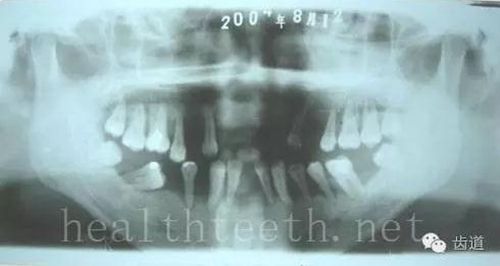

左上乳3滯留,恒3未見萌出,曲面斷層片顯示牙齒埋伏

通過CT片確定埋伏牙齒具體的位置,顯示距離左側(cè)上頜竇很近,偏唇側(cè),這為手術(shù)定位提供了方便